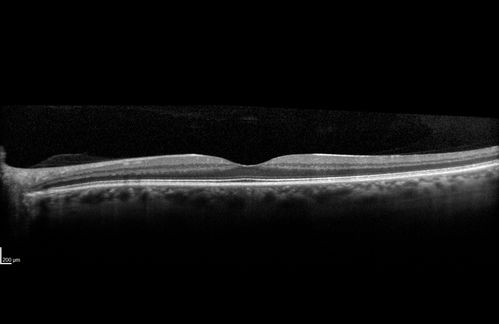

Severe outer retinal atrophy and RPE non-geographic atrophy from syphilis.  Vision improved from 20/63 to 20/32 with therapy.  Images look a lot like DUSN.  Patient had several surgeries (vitrectomy for floaters, vitrectomy for macular pucker, Avastin injections and macular laser for edema) prior by other retina specialists prior to being correctly diagnosed and treated.

Syphilitic Chorioretinitis